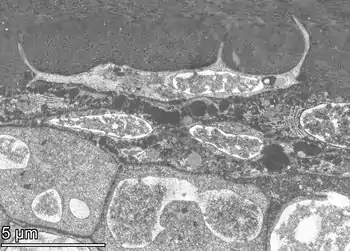

Osteocytes have a stellate shape, approximately 7 micrometers deep and wide by 15 micrometers in length.[3] The cell body varies in size from 5-20 micrometers in diameter and contain 40-60 cell processes per cell,[4] with a cell to cell distance between 20-30 micrometers.[3] A mature osteocyte contains a single nucleus that is located toward the vascular side and has one or two nucleoli and a membrane.[5] The cell also exhibits a reduced size endoplasmic reticulum, Golgi apparatus and mitochondria, and cell processes that radiate largely towards the bone surfaces in circumferential lamellae, or towards a haversian canal and outer cement line typical of osteons in concentric lamellar bone.[5] Osteocytes form an extensive lacunocanalicular network within the mineralized collagen type I matrix, with cell bodies residing within lacunae, and cell/dendritic processes within channels called canaliculi.[6]